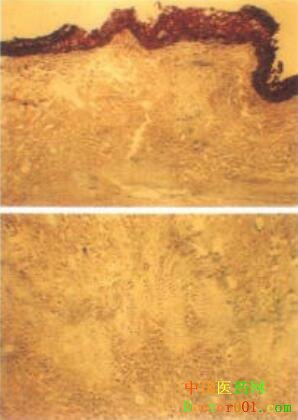

【標題】 川芎 【拼音】 Chuanxiong 【概述】 為傘形科植物川芎Ligusticum chuanxiong Hort.的根莖。主產于四川、貴州、云南,以四川產者質優。系人工栽培。5月采挖,除去泥沙,曬后烘干,再去須根。用時切片生用或酒炙。 【性味歸經】 辛,溫。歸肝、膽、心包經。 【功效】 活血行氣,祛風止痛。 【應用】 1.血瘀氣滯痛證。本品辛散溫通,既能活血化瘀,又能行氣止痛,為“血中之氣藥”,具通達氣血功效,故治氣滯血瘀之胸脅、腹部諸痛。若治心脈瘀阻之胸痹心痛,常與丹參、桂枝、檀香等同用;若治肝郁氣滯之脅痛,常配柴胡、白芍、香附,如柴胡疏肝散(《景岳全書》);如肝血瘀阻,積聚痞塊、胸脅刺痛,多與桃仁、紅花等同用,如血府逐瘀湯(《醫林改錯》)。若治跌仆損傷,瘀腫疼痛,可配乳香、沒藥、三七等藥用。 川芎善“下調經水,中開郁結”,為婦科要藥,能活血調經,可用治多種婦產科的疾病。如治血瘀經閉,痛經,常與赤芍、桃仁等同用,如血府逐瘀湯(《醫林改錯》);若屬寒凝血瘀者,可配桂心、當歸等,如溫經湯(《婦人大全良方》);若治產后惡露不下,瘀阻腹痛,可配當歸、桃仁、炮姜等,如生化湯(《傅青主女科》);若治月經不調,經期超前或錯后,可配益母草、當歸等,如益母勝金丹(《醫學心悟》)。 2.頭痛,風濕痹痛。本品辛溫升散,能“上行頭目”,祛風止痛,為治頭痛要藥,無論風寒、風熱、風濕、血虛、血瘀頭痛均可隨證配伍用之,故李東垣言“頭痛須用川芎”。治風寒頭痛,配羌活、細辛、白芷,如川芎茶調散(《和劑局方》);若配菊花、石膏、僵蠶,可治風熱頭痛,如川芎散(《衛生保健》);若治風濕頭痛,可配羌活、獨活、防風,如羌活勝濕湯(《內外傷辨惑論》);配當歸、白芍,取本品祛風止痛之功,可治血虛頭痛,如加味四物湯(《金匱翼》);若治血瘀頭痛,可配赤芍、麝香,如通竅活血湯(《醫林改錯》)。 本品辛散溫通,能祛風通絡止痛,又可治風濕痹痛,常配獨活、秦艽、防風、桂枝等藥同用,如獨活寄生湯(《千金方》)。 【注意】 陰虛火旺,多汗,熱盛及無瘀之出血證和孕婦慎用。 【用法用量】 煎服,3~9g。 【臨床研究】 1.化學成分:本品含生物堿(如川芎嗪),揮發油(主要為藁本內脂、香燴烯等),酚類物質(如阿魏酸),內脂素以及維生素A,葉酸,蔗糖,甾醇,脂肪油等。 2.藥理作用:川芎嗪能擴張冠狀動脈,增加冠狀動脈血流量,改善心肌的血氧供應,并降低心肌的耗氧量;川芎嗪可擴張腦血管,降低血管阻力,顯著增加腦及肢體血流量,改善微循環;能降低血小板表面活性,抑制血小板凝集,預防血栓的形成,;所含阿魏酸的中性成分小劑量促進,大劑量抑制子宮平滑肌;水煎劑對動物中樞神經系統有鎮靜作用,并有明顯而持久的降壓作用;可加速骨折局部血腫的吸收,促進骨痂形成;有抗維生素E缺乏作用;能抑制多種桿菌;有抗組織胺和利膽作用。 3.臨床研究: 川芎在臨床上應用廣泛。如:用川芎、紅花各等份壓片,每天口服3次,每次4片(每片含川芎、紅花各1.25 克),治療冠心病心絞痛84例,83例有效。(北京地區冠心病協作組。資料匯編(第二輯),1972,12)。每日用川芎嗪80—100毫升加入5%葡萄糖液500毫升靜滴1次,10次為1療程,治療缺血性中風急性期66例,恢復期154例,后遺癥期47例。結果:急性期有效率100%,恢復期有效率95.4%,后遺癥期有效率70.2%。(陜西中醫,1988.(9):408)。用川芎24—28克,白酒30毫升,水250毫升,浸泡1小時后,加蓋用文火燉煎分2次服,不飲酒者可單加水燉服,治療功能性子宮出血29例,均有效(陜西中醫,1990,11(4):150)。 【參考文獻】 1.《神農本草經》:“主中風入腦頭痛、寒痹,筋脈緩急,金瘡,婦人血閉無子。” 2.《本草匯言》:“芎艸穹,上行頭目,下調經水,中開郁結,血中氣藥。嘗為當歸所使,非第治血有功,而治氣亦神驗也……味辛性陽,氣善走竄而無陰凝粘滯之態,雖入血分,又能去一切風,調一切氣。” 3.《本草新編》:“川芎……血閉者能通,外感者能散,療頭風其神,止金瘡疼痛。此藥可君可臣,又可為佐使,但不可單用……倘單用一味以補血,則血動,反有散失之憂。若單用一味以止痛,則痛止,轉有暴亡之慮。” 【圖片】 川芎 ![]() 川芎《中藥學》 ![]() 川芎《本草綱目》 ![]() 川芎植株 ![]() 川芎藥材及飲片 ![]() 藥材川芎 ![]() 藥材川芎橫切面 ![]() 藥材川芎片 ![]() 【表格】 川芎《中藥歌決》 【歌決】 川芎辛溫包肝膽,破瘀通經解痙攣; 頭痛腦脹血壓高,腹痛筋攣臟燥煩。 (責任編輯:Doctor001) |